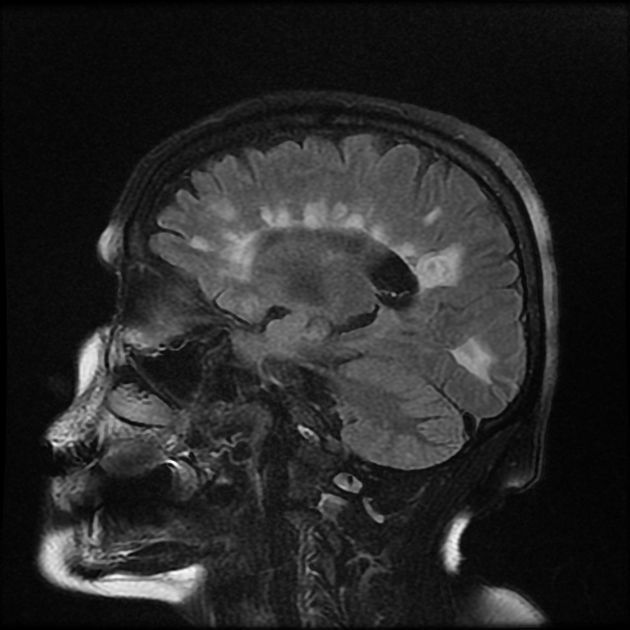

Many modalities of MRI are essential in diagnosis of multiple sclerosis. These sequences are discussed as follows: 1. T1 - Isointense to hypointense lesion - Thin corpus callosum - Hyperintense lesions when associated with brain atrophy 2. T2 - Hyperintense lesion - Edema surrounds the lesion 3. SWI - Central vein sign 4. FLAIR - Hyperintense lesions - Ependymal dot-dash sign - Dawson’s fingers 5. T1 C+ - Enhanced active lesions - Open ring sign 6. DWI/ADC - High or low ADC in active lesion 7. MR Spectroscopy - Reduced NAA peaks in plaques - Increased choline and lactate in acute phase Reference: https://radiopaedia.org/articles/multiple-sclerosis Image via: https://radiopaedia.org/articles/dawson-fingers